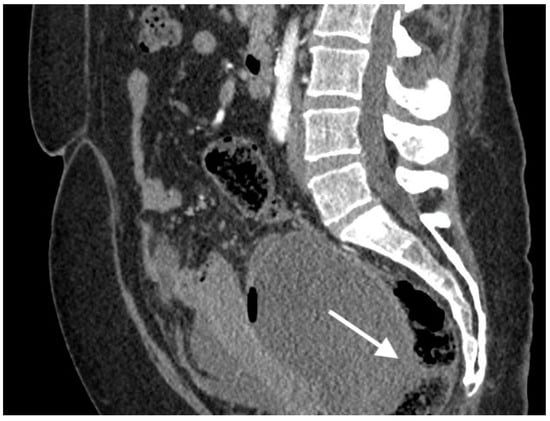

Figure 1.

Images from 58-year-old patient with carcinosarcoma of the ovary and recurrence in the rare form of giant cell carcinoma. The fistula between tumor and rectum (arrow), CT post-contrast image in venous phase obtained in the axial plane, shows pelvic tumor and adjacent intestine, fatty tissue between the tumor and intestine vanished as indirect sign of the fistula.

The median diameter of the relapsed tumor was 89 mm (range 36–130 mm). In all cases, fistulas formed between the tumor and large bowel. In three cases, fistulas formed between the rectum, including two between the sigmoid colon, one sigmoid and descending colon, one between the cecum and ascending colon, and one between the sigmoid colon and left ureter. On CT, in all cases, the fistulas were not directly visible, with only indirect signs of the fistula observed, such as infiltration of the intestine by the tumor, which we observed as vanishing of the fatty tissue between the tumor and the description of the intestinal wall, disruption of the intestinal wall, or the presence of gas in the tumor. In five patients, we observed thickening of the intestinal wall associated with a fistula (Figure 1, Figure 2 and Figure 3).

On computed tomography, we observed only indirect imaging signs of fistulas, such as infiltration of the intestine by the tumor, which we observed as vanishing of the fatty tissue between the tumor and the intestine, disruption of the intestinal wall, and gas in the tumor. Computed tomography’s limitation is evident when evaluating local tumor spread due to its lower soft tissue resolution. In other studies, CT was very useful for diagnosis, revealing indirect signs of fistulas, such as obvious thickening of the tumor wall and an air-fluid level within the tumor, suggesting that the ovarian tumor might have communication with the digestive tract; however, they also did not observe fistulas directly [11].